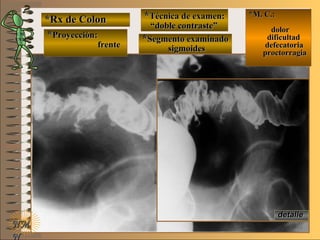

*Rx de Estómago*Rx de Estómago

**Proyección:Proyección:

**Técnica de examen:Técnica de examen:

A-A-

B-B-

C-C-